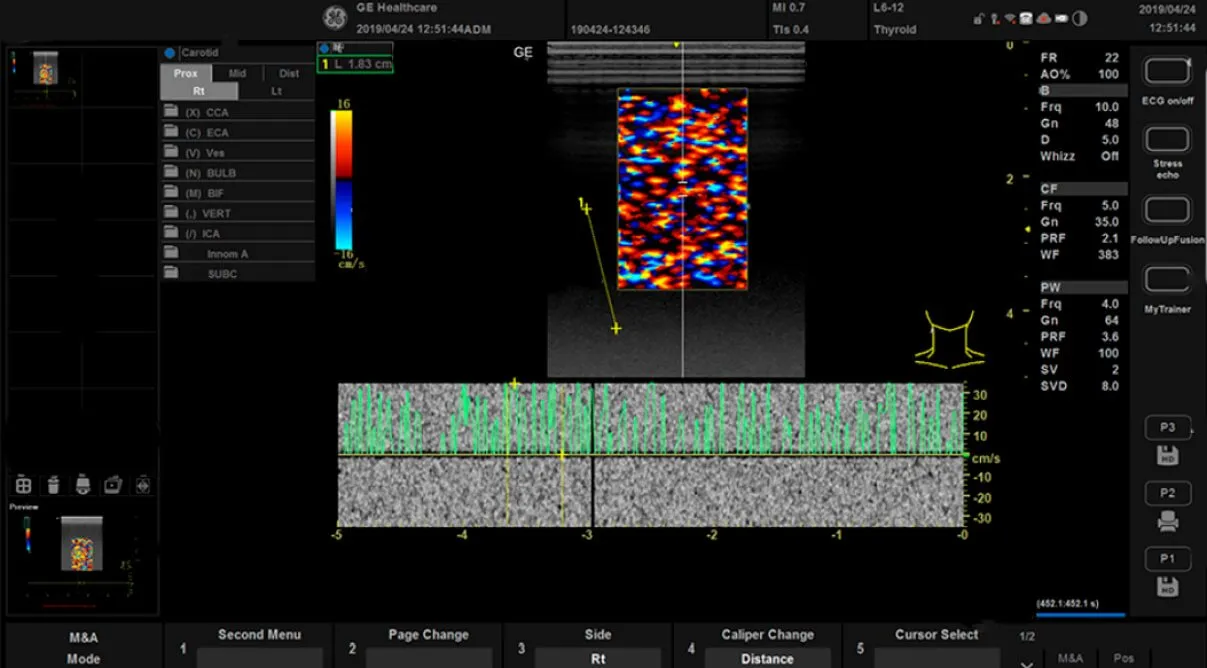

GE HealthCare

GE HealthCare